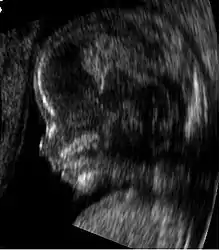

Sonogram of a fetus at 14 weeks (profile)

The potential for ultrasonic imaging of objects, in which a 3 GHz sound wave could produce resolution comparable to an optical image, was recognized by Sergei Sokolov in 1939. Such frequencies were not possible at the time, and what technology did exist produced relatively low-contrast images with poor sensitivity.[34] Ultrasonic imaging uses frequencies of 2 megahertz and higher; the shorter wavelength allows resolution of small internal details in structures and tissues. The power density is generally less than 1 watt per square centimetre to avoid heating and cavitation effects in the object under examination.[35] Ultrasonic imaging applications include industrial nondestructive testing, quality control and medical uses.[34]

Medical ultrasound is an ultrasound-based diagnostic medical imaging technique used to visualize muscles, tendons, and many internal organs to capture their size, structure and any pathological lesions with real time tomographic images. Ultrasound has been used by radiologists and sonographers to image the human body for at least 50 years and has become a widely used diagnostic tool. The technology is relatively inexpensive and portable, especially when compared with other techniques, such as magnetic resonance imaging (MRI) and computed tomography (CT). Ultrasound is also used to visualize fetuses during routine and emergency prenatal care. Such diagnostic applications used during pregnancy are referred to as obstetric sonography. As currently applied in the medical field, properly performed ultrasound poses no known risks to the patient.[36] Sonography does not use ionizing radiation, and the power levels used for imaging are too low to cause adverse heating or pressure effects in tissue.[37][38] Although the long-term effects due to ultrasound exposure at diagnostic intensity are still unknown,[39] currently most doctors feel that the benefits to patients outweigh the risks.[40] The ALARA (As Low As Reasonably Achievable) principle has been advocated for an ultrasound examination  that is, keeping the scanning time and power settings as low as possible but consistent with diagnostic imaging  and that by that principle nonmedical uses, which by definition are not necessary, are actively discouraged.[41]